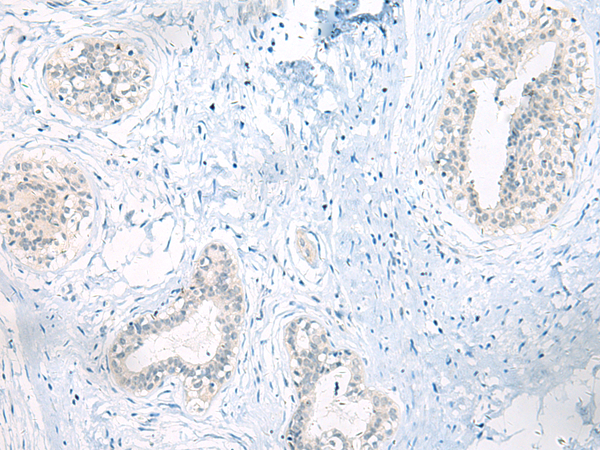

分类: 科研抗体货号: P13565别名: EULIR应用: IHC反应种属: Human, Mouse